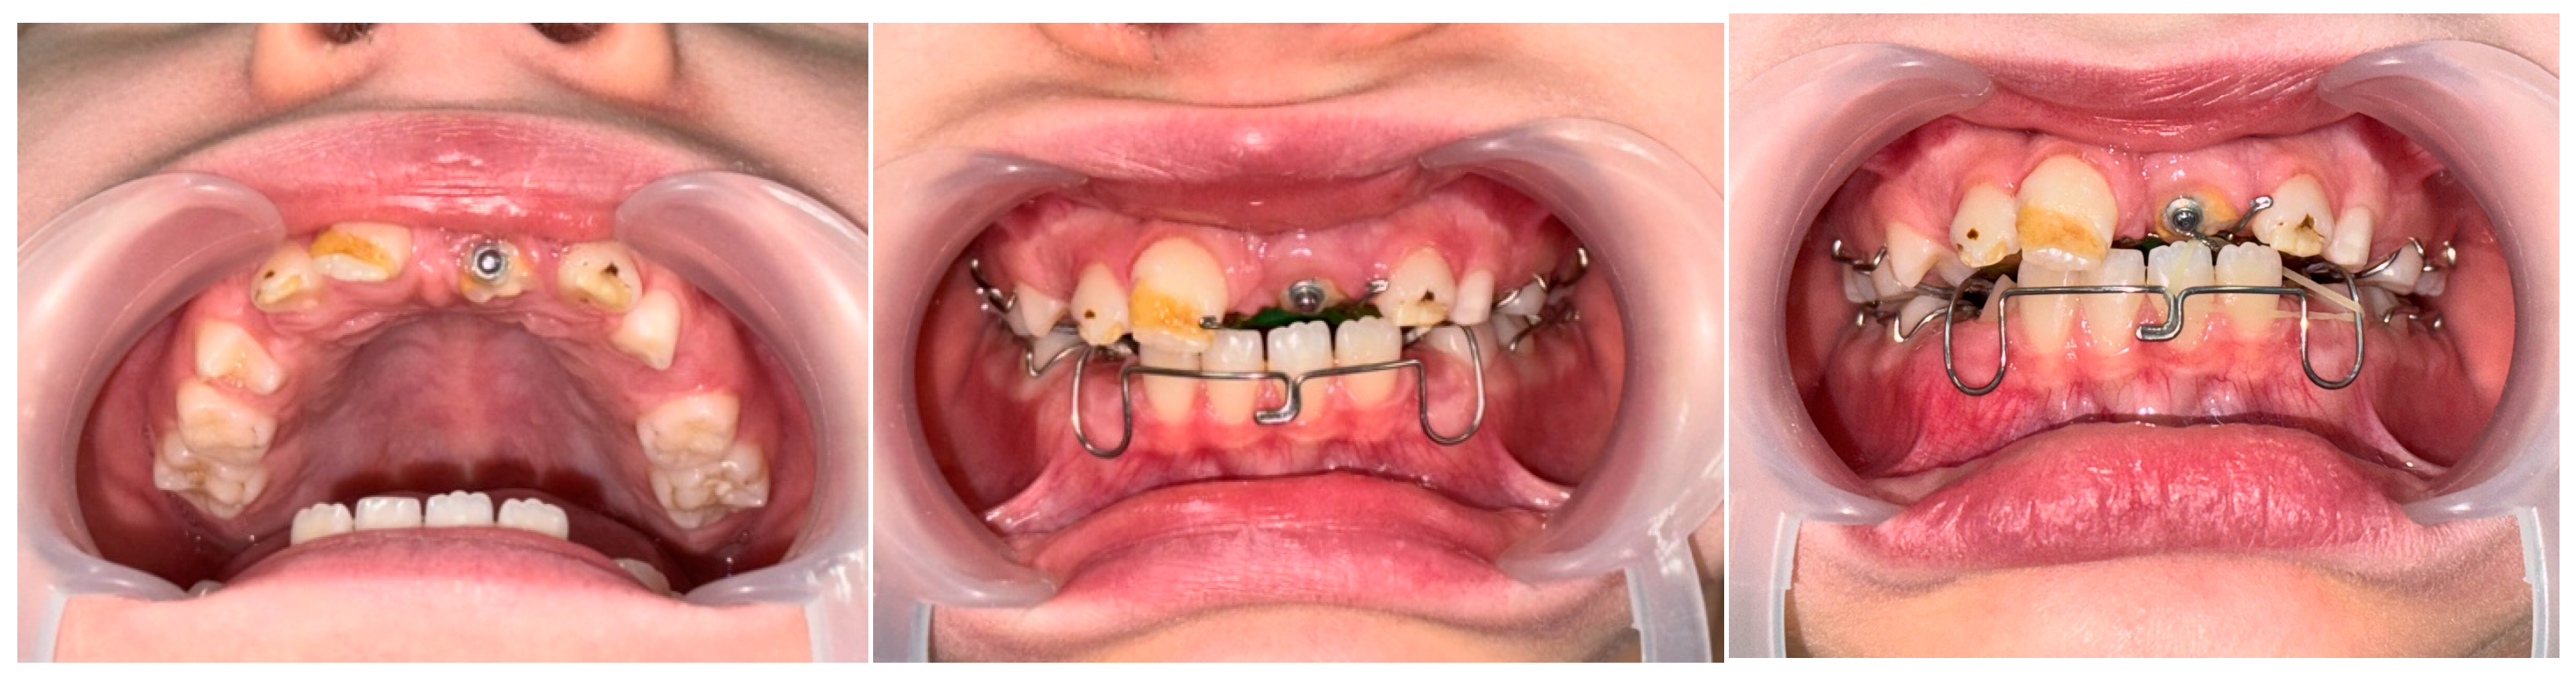

2. Case Presentation